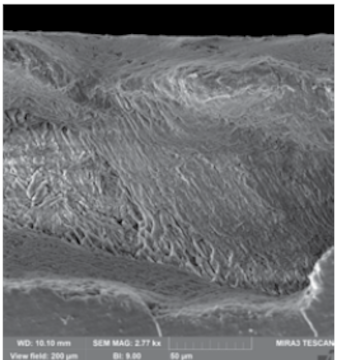

A recent in vitro study (n=3) evaluated the effect of treating early caries lesions with one application of CurodontTM

and demonstrated hydroxyapatite generation throughout the depth of the lesion within as little as 2 weeks

A statistically significant average increase of 15% in mineral density throughout the lesion was observed within only 2 weeks (p<0.001)***, independently of the lesion depth

An exemplary depth profile up to 90% of the initial lesion.

Depth was measured at 20um, 50um and full depth (100um).

In all cases, a statistically significant increase in mineral density seen throughout the lesion.

***The p-value is calculated based on averages and standard deviations which allows to draw a conclusion on statistical significance.

Data on file (2025), vVARDIS funded in vitro study

A recent study demonstrated that Curodont Repair Fluoride Plus led to a significant increase in mineral density throughout the lesion depth within only 2 weeks using Micro-CT and Scanning Electron Microscope analysis. [Cowen M et al. Biomater Res Rep 2025 Aug;175 Curodont™ Repair Fluoride Plus – Dental Advisor (Accessed 04/28/2026)]